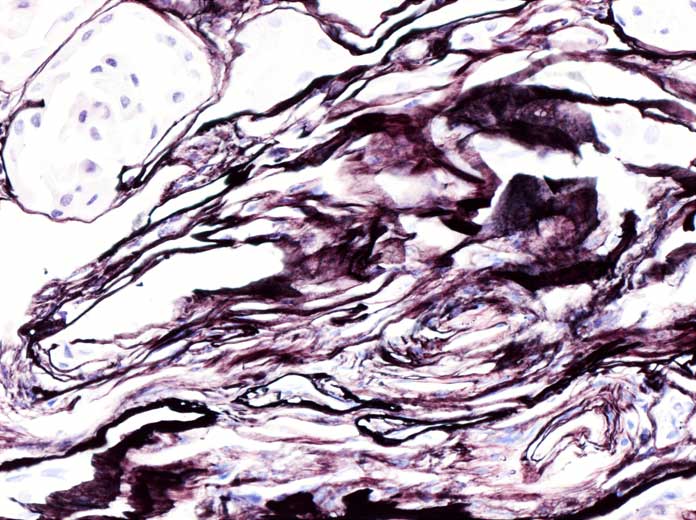

Případ č.6 - PM 17678/02

Muž, 41 let, lékař!-vlastní ledvina

KO: 3 týdny se vyvíjely otoky dolních končetin, poté selhání ledvin. Proteinurie 5g/24 hodin. Mitrální insuficience. Pacient připouští zvýšený krevní tlak. Diabetes neguje.

IF: tečkovitá necharakteristická pozitivita C3 v epitelu glomerulů, fibrin pozitivní v kličkách.  IgA, IgG, IgM, kappa, lambda-vše negativní